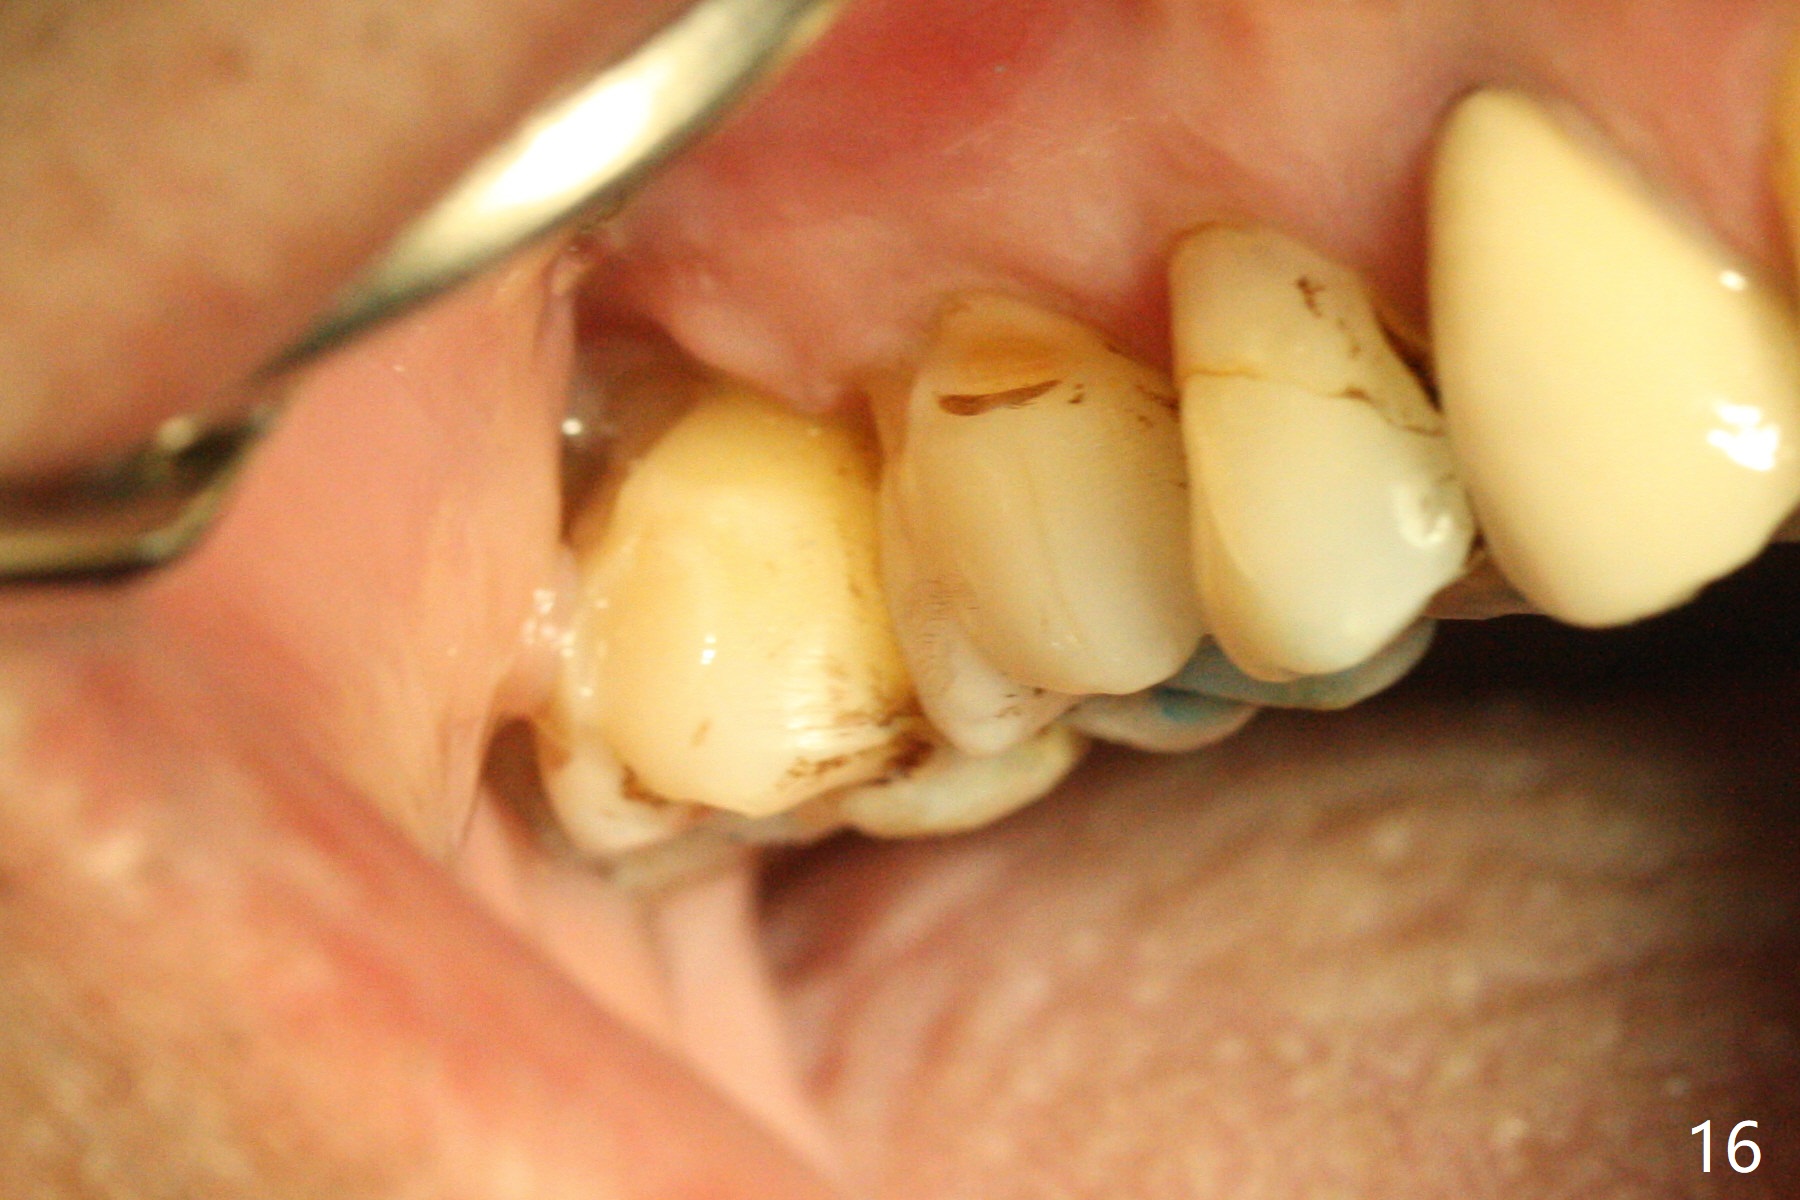

The buccal implant becomes loose in 2-3 months. When the wound heals (Fig.9 <), a 1.6x`10 mm implant is placed with the help of PAs for trajectory (Fig.10,11) and in the nonkeratinized gingiva (higher, the crestal bone may have been traumatized by previous implant placement, Fig.12). Two months later, the tooth #2 is partially intruded (Fig.13). A provisional (Fig.14 P) is fabricated in the osteointegrated implant at #31 with supraocclusion so that the remaining dentition has no occlusal contact (*). The periodontally compromised tooth #2 becomes in buccoversion in 2 months. The provisional is removed, while a lingual button is placed in the buccal surface of the tooth #2 (Fig.15). With power chain attached to the lingual mini-implant, the tooth #2 is lingualized in 2 months. The provisional and the implants are reused for final intrusion (Fig.16). The treatment is nearly 11 months. The buccal implant, although placed in the movable mucosa, remains stable and healthy (Fig.17). The tooth #1, as a guiding plane (to prevent #2 from distalization during intrusion), is not extracted after intrusion is completed.